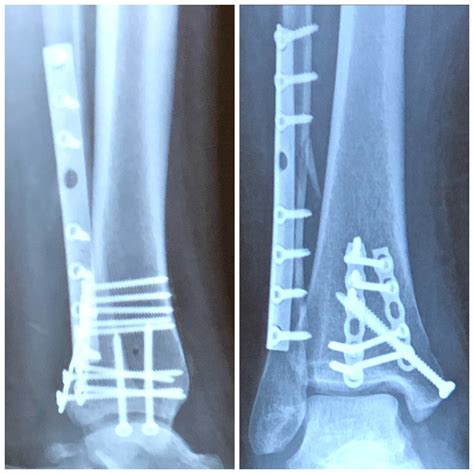

For most simple fractures, patients may expect to be back to light activities within 3 to 4 months, while more complex fractures requiring surgical intervention (ORIF - Open Reduction Internal Fixation) may extend the ankle fracture rehabilitation time to 6 to 12 months for a complete return to high-impact activities.